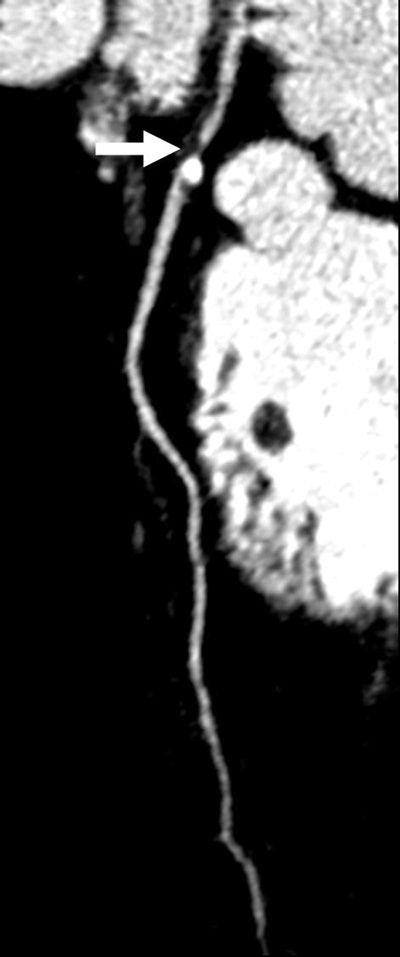

| Images 1-7 shown top to bottom: A 59-year-old man presented with atypical chest pain. A circumscribed, short-segment high-degree stenosis (arrow) in the proximal LAD is difficult to detect on transverse (1), sagittal (2), or coronal (3) multiplanar reformats. Use of advanced visualization tools with automated extraction of the coronary artery tree (4) and automated display as curved multiplanar reformat (5) clearly identifies the lesion, also seen in the 3D view (6) and confirmed on conventional catheter angiography (7). All images courtesy of Dr. U. Joseph Schoepf. |